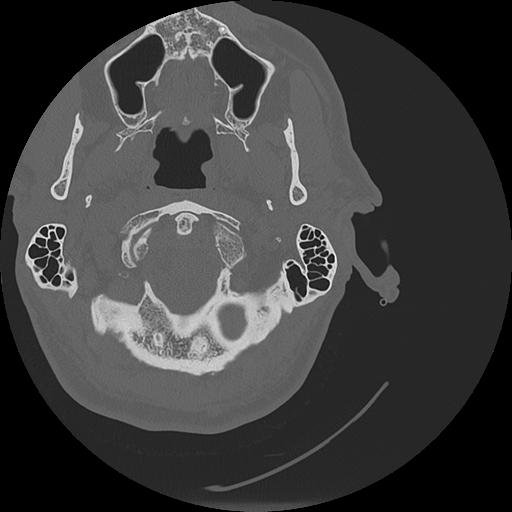

7 HUESO,,Vol,0.5,HUESO,,